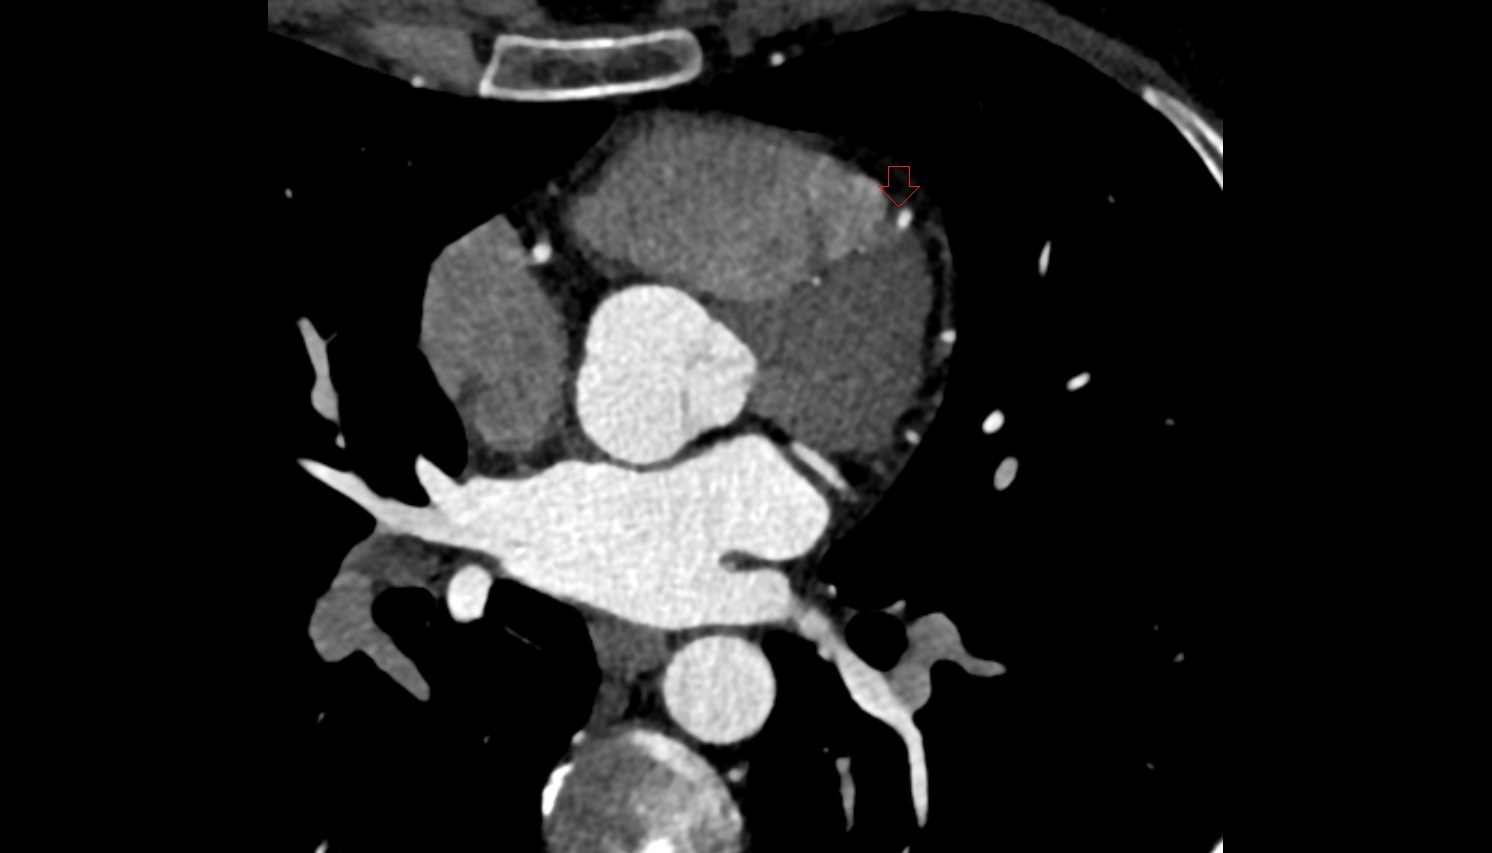

- Left anterior descending artery (LAD)

- Circumflex artery (LCx)

- Left main coronary artery (LMCA)

- Right coronary artery (RCA)